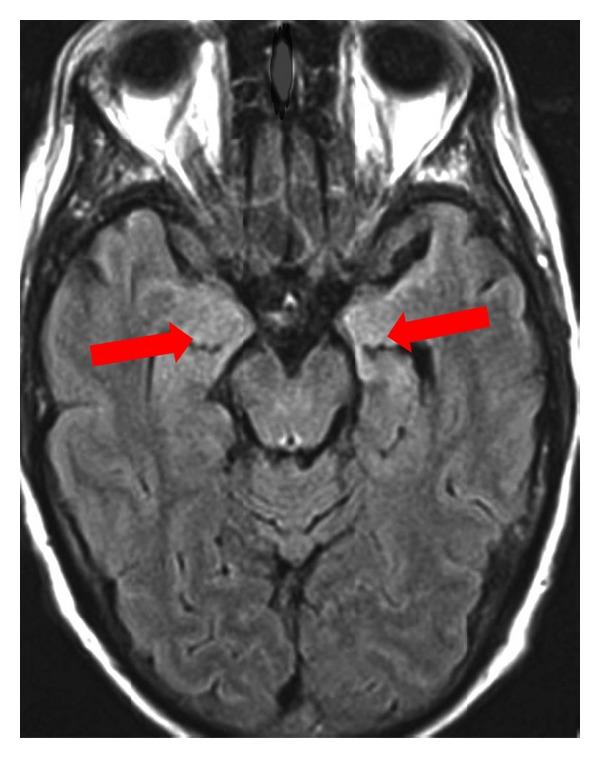

Paraneoplastic neurological syndromes (PNSs) occur in patients with cancer and can cause clinical symptoms and signs of dysfunction of the nervous system that are not due to a local effect of the tumor or its metastases. Most of these clinical syndromes in adults are associated with lung cancer, especially small cell lung cancer (SCLC), lymphoma, and gynecological tumors. The finding of highly specific antibodies directed against onconeural antigens has revolutionized the diagnosis and promoted the understanding of these syndromes and led to the current hypothesis of an autoimmune pathophysiology. Accumulating data strongly suggested direct pathogenicity of these antibodies. The field of PNS has expanded rapidly in the past few years with the discovery of limbic encephalitis associated with glutamic acid decarboxylase (GAD) 65, the voltage (VGKC-gated potassium channel) complex, the methyl (N-NMDA-D-aspartate), alpha-amino-3-hydroxy-5-methyl-4-isoxazolepropionic acid (AMPA), and gamma aminobutyric acid (GABA) (B) receptors, and so forth. Despite this, the clinical spectrum of these diseases has not yet been fully investigated. The clinical importance of these conditions lies in their frequent response to immunotherapies and, less commonly, their association with distinctive tumors. This review provides an overview on the pathogenesis and diagnosis of PNS, with emphasis on the role of antibodies in limbic encephalitis.